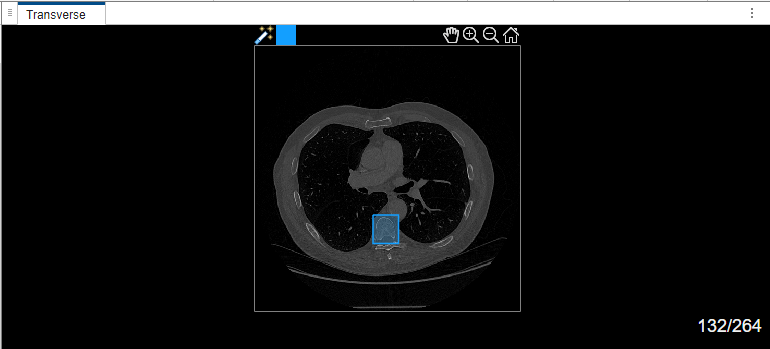

Select label Type1. Draw a bounding box around the object to segment in the transverse plane of the volume.

If you are segmenting objects in a medical image or a 2-D slice image of a medical volume for the first time in the app, and if you are not using a GPU, the MedSAM algorithm takes some time to extract embeddings for the image. In this case, the app displays the Running MedSAM model dialog box.

Once the MedSAM algorithm extracts the embeddings of the image, you can adjust the bounding box.